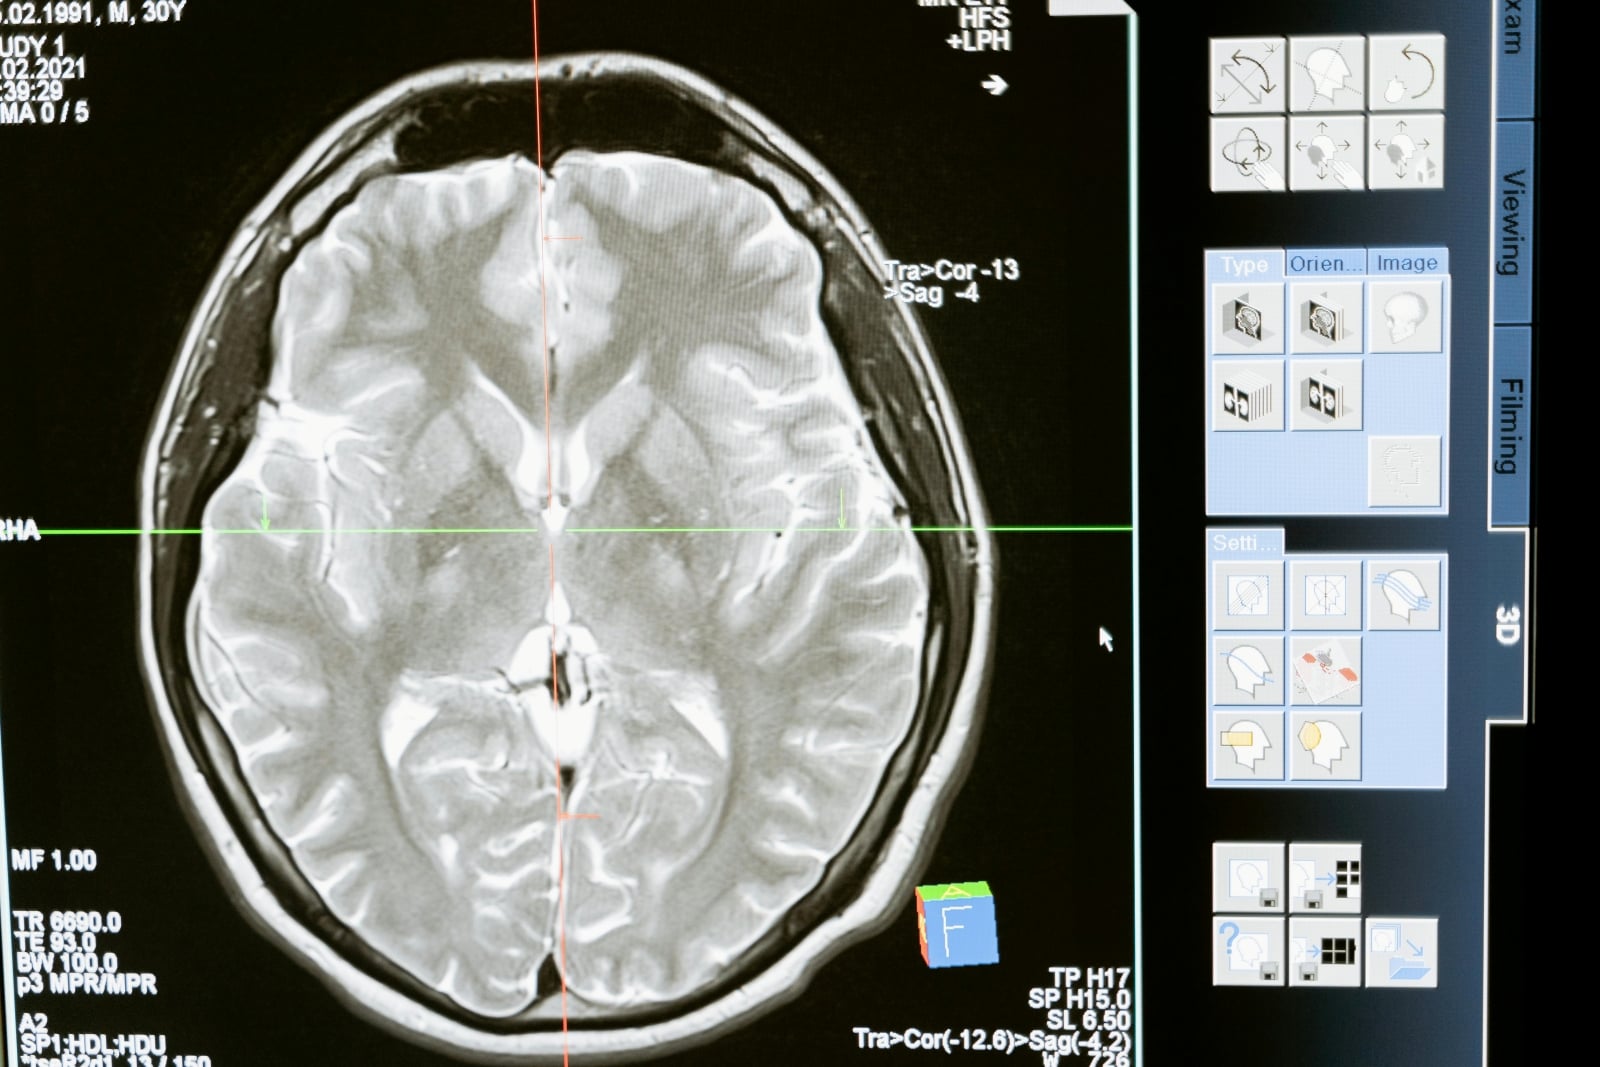

Ako informuje web IFL Science, na základe štúdia skenov mozgov takmer 4 000 ľudí z celého spektra ľudského života, od novorodencov po 90-ročných ľudí, identifikoval tím odborníkov 4 „zlomové body“, v ktorých mozog prechádza zásadnými zmenami. Rozdeľujú jeho životnosť do piatich období, informujú v štúdii publikovanej prostredníctvom Nature Communications.

Dáta ukazujú, že kľúčový je vek 9, 32, 66 a 83 rokov. „Vieme, že prepojenia v mozgu sú kľúčové pre náš vývoj, ale chýba nám celkový obraz o tom, ako sa mení v priebehu nášho života, a prečo. Táto štúdia je prvou, ktorá identifikuje hlavné fázy zmien,“ uviedla vo vyhlásení hlavná autorka štúdie Alexa Mousley.